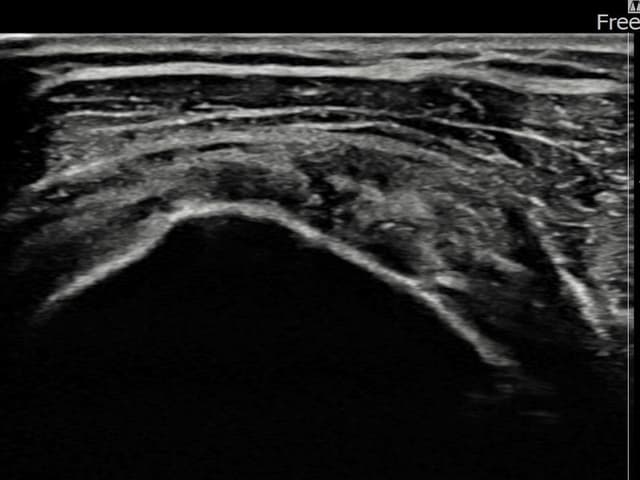

[経過期間: 24.03.21~24.05.29]

[縫縮術] 超音波検査にて右 견갑하근건 部分断裂(8mm × 3mm (腱厚の約32%欠損))を確認。縫縮術施行後、腱の連続性が回復し、日常生活に復帰されました。